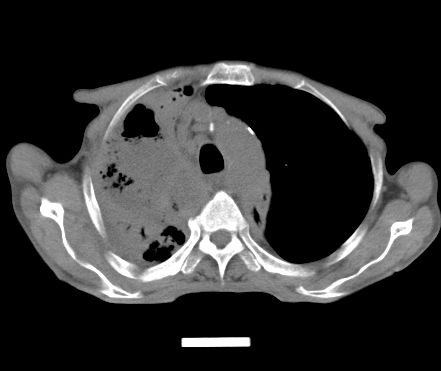

以下是引用gaoshengjiang在2008-5-30 19:53:00的发言:[br]右上叶可见大片实变影,其内可见充气支气管影及囊状影,右上叶尖端支气管走形区可见结节样影,左侧胸腔内可见胸腔胃影。纵隔淋巴结肿大。[br]考虑:1.右上肺阻塞性肺炎伴肺脓肿形成。支持转移所致。[br] 2.左侧胸腔胃。